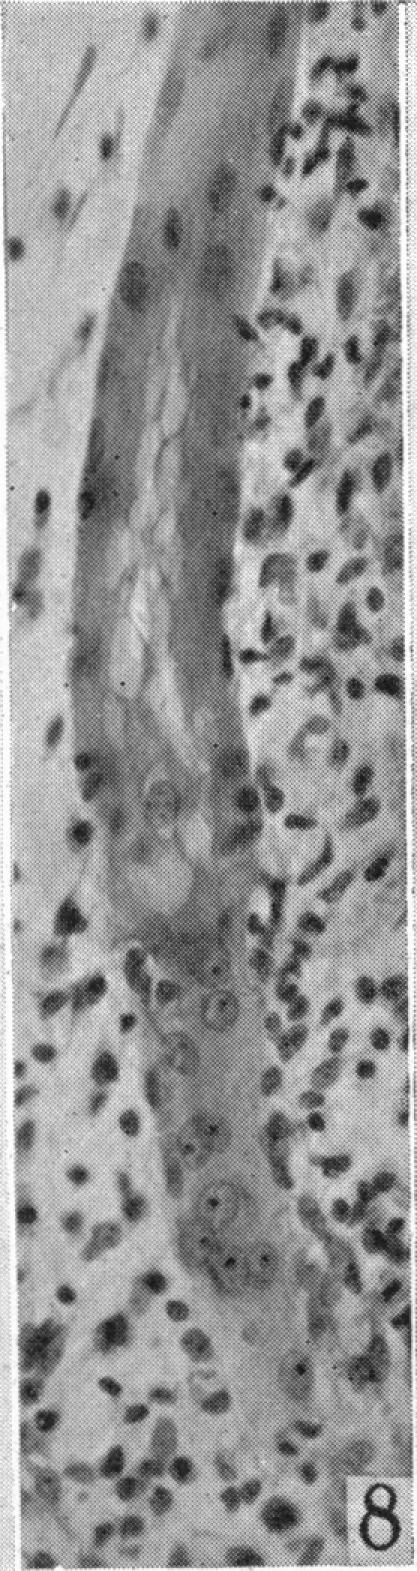

An experimental study of the regeneration of mammalian striped muscle.

摘要